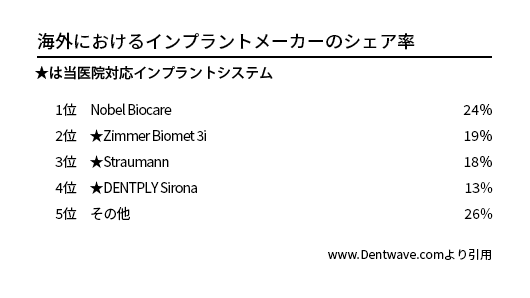

200社を超える世界のインプラントメーカー

現在、世界には200社を超えるインプラントメーカーが存在し、日本へは厚生労働省認可としては約30社のものが認められています。それ以外は歯科医の個人責任による個人輸入です。正直、よく分からない某国メーカーや、いつのまにか撤退、倒産、消滅していて、アフターケアが不可能になるものや、中には劣悪な製品ゆえの長期安定性に欠けるものも存在します。世界的な知名度、シェアを有していても日本では無名であるものや、逆に日本では知名度、シェア有していても世界的には無名なものもあり、一概には判断できません。中には無茶苦茶なディスカウントを行うメーカーや、安価をうたいつつもメーカー自体非常に怪しいものなど、販売方法に疑問があるメーカーも存在します。また、メーカー自体が倒産してしまったものもありますが、このような場合、消耗品パーツの供給などアフターケアに問題が出ています。

インプラント治療を行おうとお考えの場合、歯科医院がどのようなインプラントシステムを使用しているかご確認された方が良いでしょう。もっとも「ブランドインプラント」を使用することにより、患者さんにアピールしている場合もありますので注意が必要です。あくまでも使う側、歯科医の知識、スキル、経験が大事です。